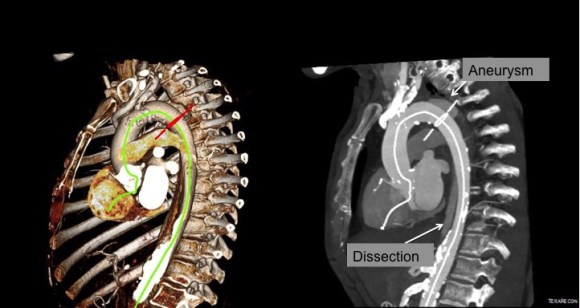

His operation was performed via an anterior approach with the patient supine. A tube graft repair was performed expeditiously and included resecting the dissection flap up to the clamp. Care was taken to avoid injury to the renal stent. The proximal anastomosis went well – the dilated aorta yet had strong tissue strength. A felt strip was used to buttress the aortic side of the anastomosis. The estimated risk of paralysis was less than 1% and risk of death was less than 2%. The patient recovered uneventfully and went home on POD 5.